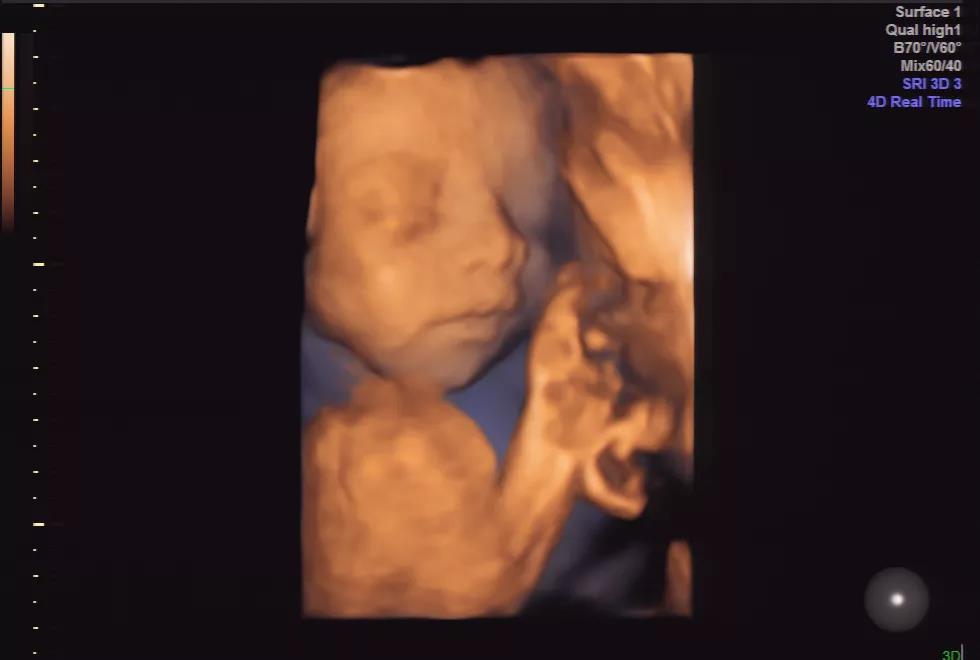

她在孕中期检查时发现

宝宝脐带绕颈2圈

根据B超检查,胎儿脐带绕颈还是2圈

呈W形,根据医生评估

在孕中期,通过孕期检查就能

及时发现脐带绕颈情况